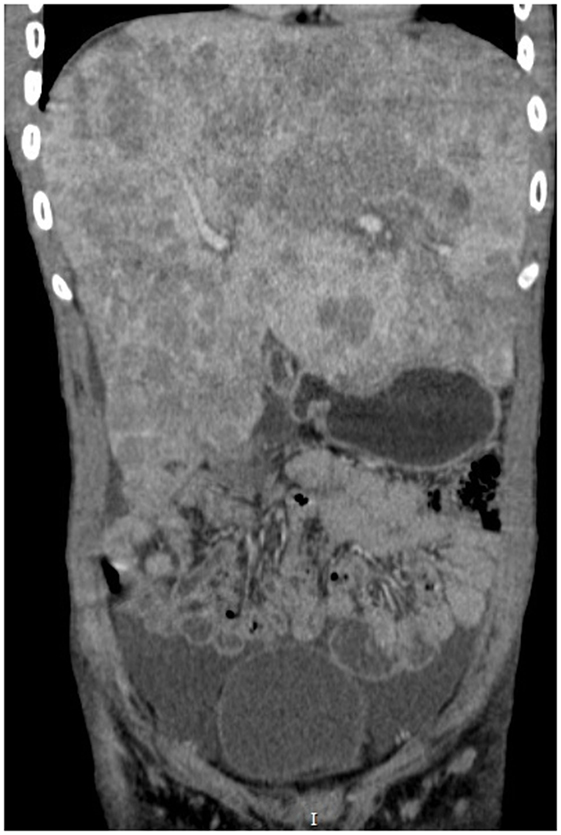

Abdominal CT scan (Figures 1 and 2) showed slight peripheral impregnation by contrast in the innumerous hypodense lesions, in addition to lymph node enlargement in the upper abdomen and pelvis. Low to moderate amount of free fluid was seen in the abdominal cavity. Besides all this complementary investigation, the patient initiate to complain about right eye pain, the blinded eye traumatized 4 months ago.

FIGURE 2

Figure 2. Abdominal CT in coronal cut showing the massive hepatomegaly.